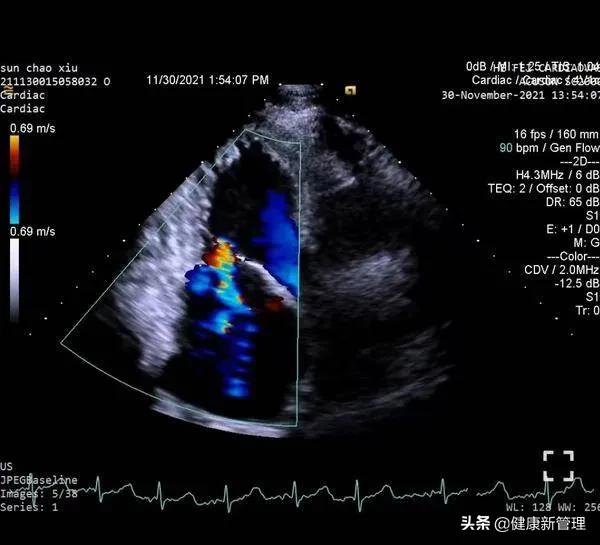

术前心脏彩超完善各项术前准备后,患者于全麻下,梅举教授主刀,经食道超声引导,经心尖送入二尖瓣夹,捕获并夹合二尖瓣前后叶病变处,二尖瓣夹位置稳定。术后超声显示,该患者二尖瓣反流即刻减少。

术中心脏彩超